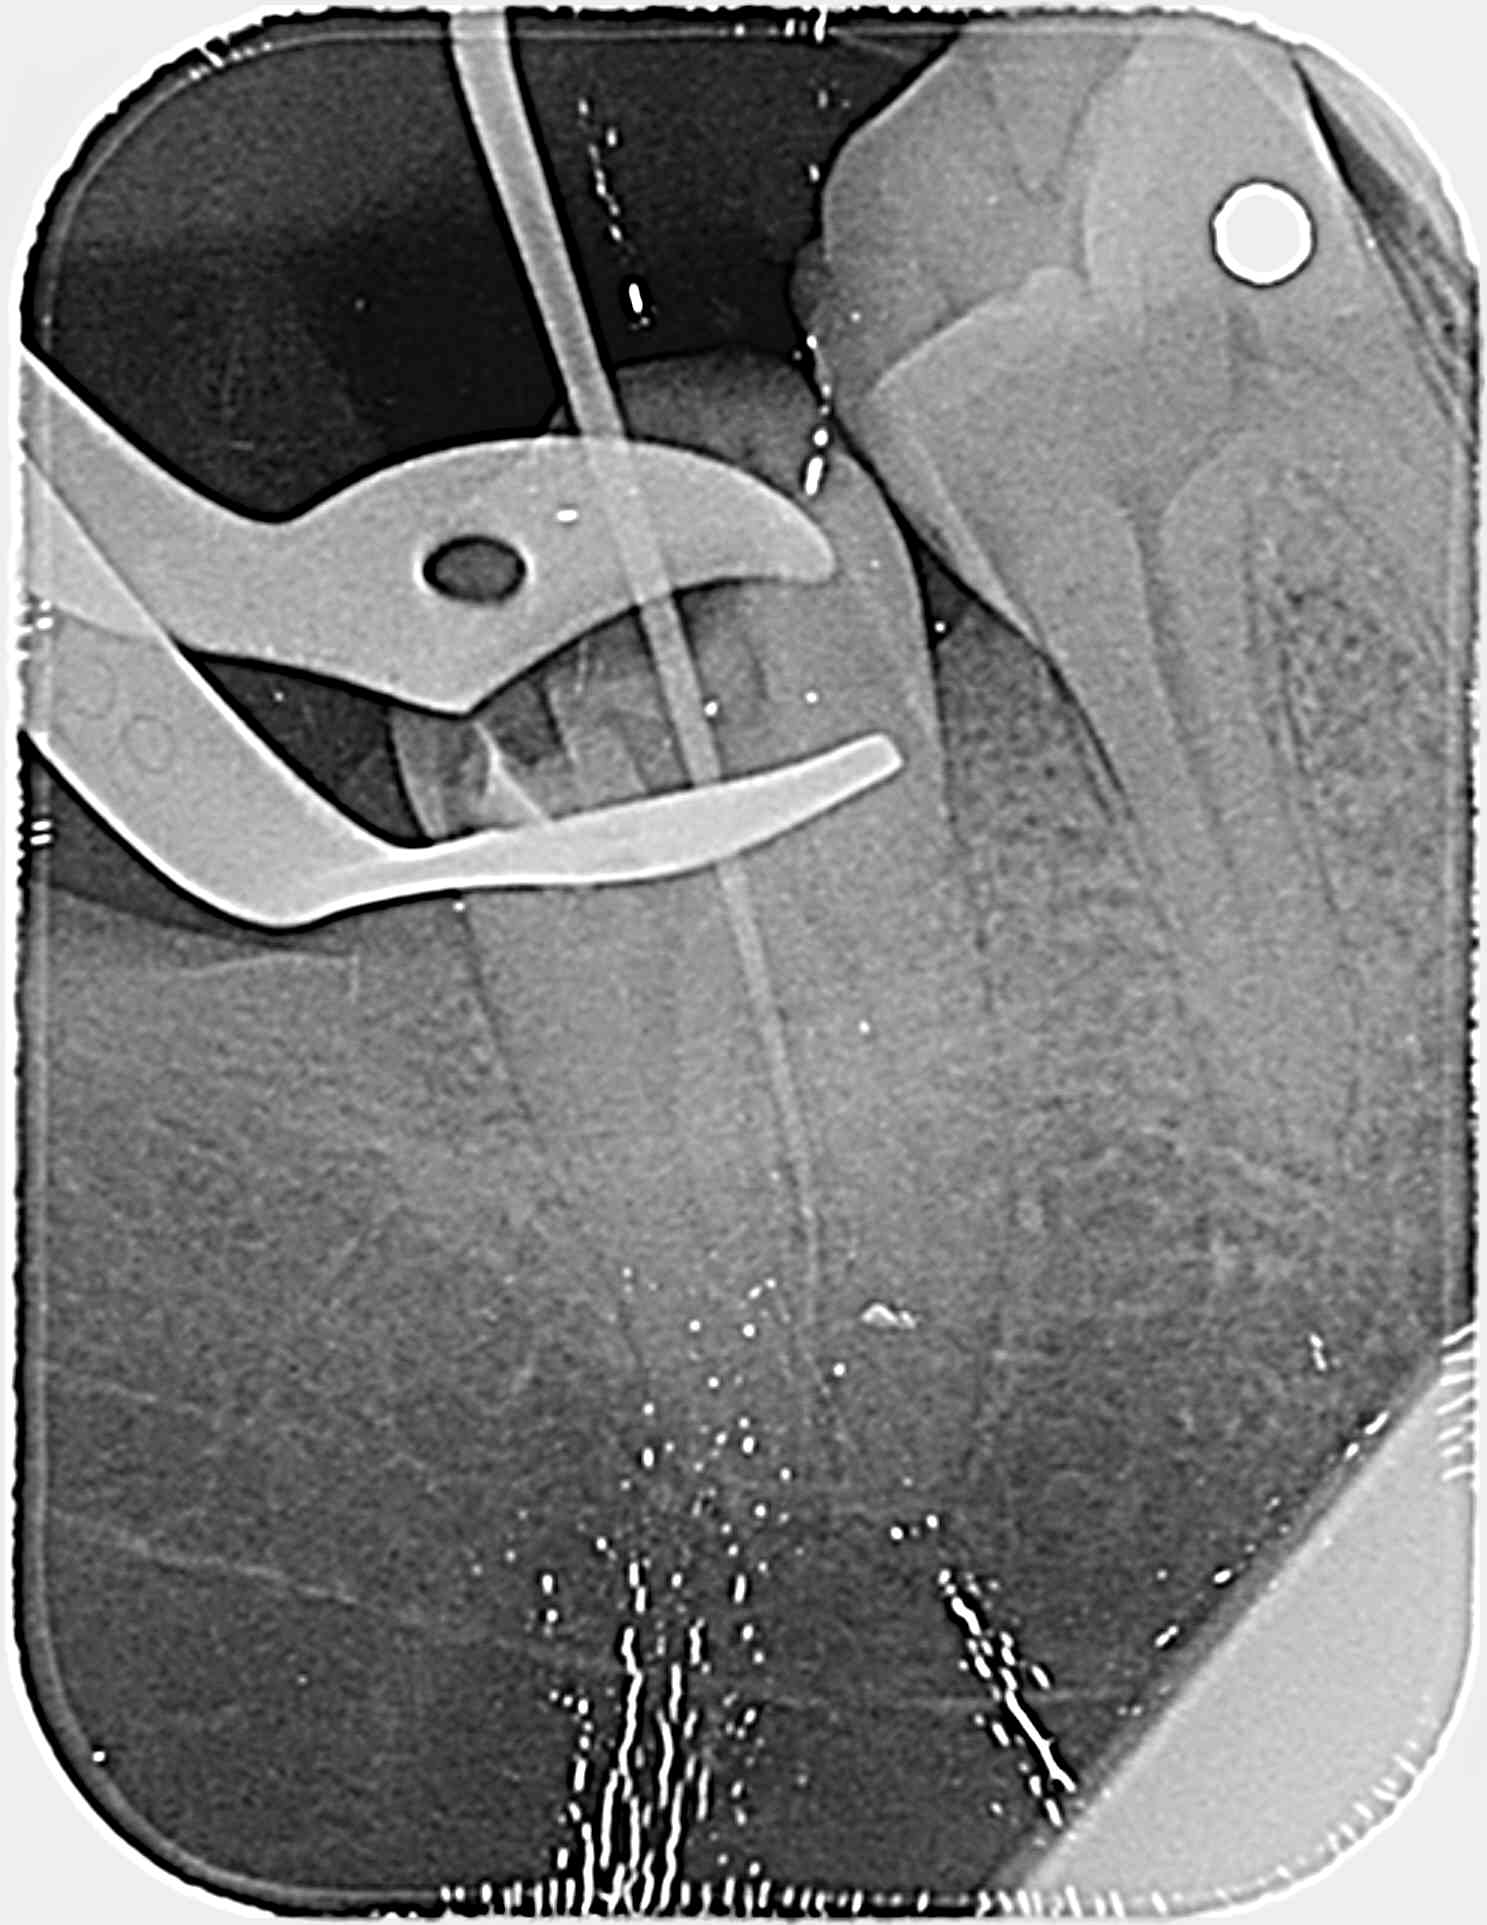

Ouverture chambre simple.

Recherche des canaux aux pathfiles et là ma radio me donne cette image improbable, avec 2 canaux distinctes.

je rejoins Vulpi, pas d saignement à l'alésage,et le localisateur qui ne bippait pas.